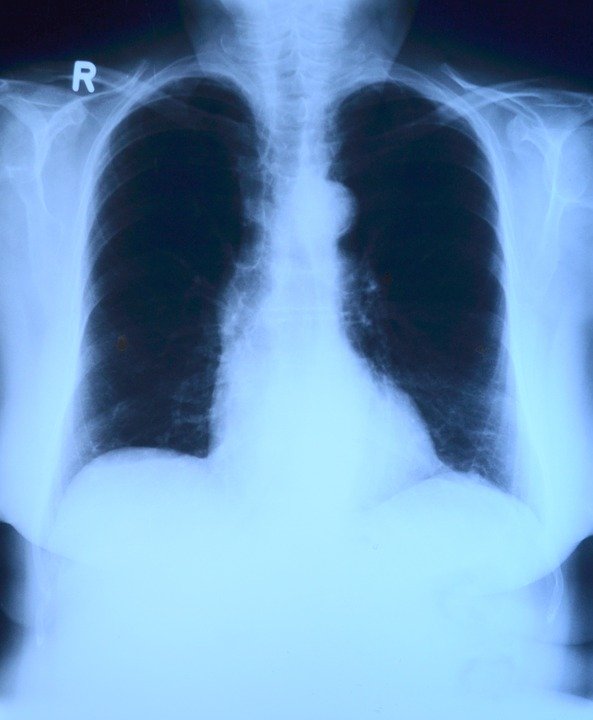

3. 위 식도 등의 소화기 질환

소화기 계통에 문제가 발생했을때 왼쪽 가슴에 통증이 발생할수있습니다. 보통 왼쪽 상체의 가슴이 쓰리거나 갈비뼈 쪽이 안좋을 경우 역류성 식도염일수있어요. 역류성 식도염의 경우에도 심장과 왼쪽 가슴 부분에서 통증이 느껴지는데요.

음식을 먹었을 때나 눕거나 목을 숙이는 자세에서 통증이 더 심해진다고 하면 이 질환을 의심해볼수있습니다.